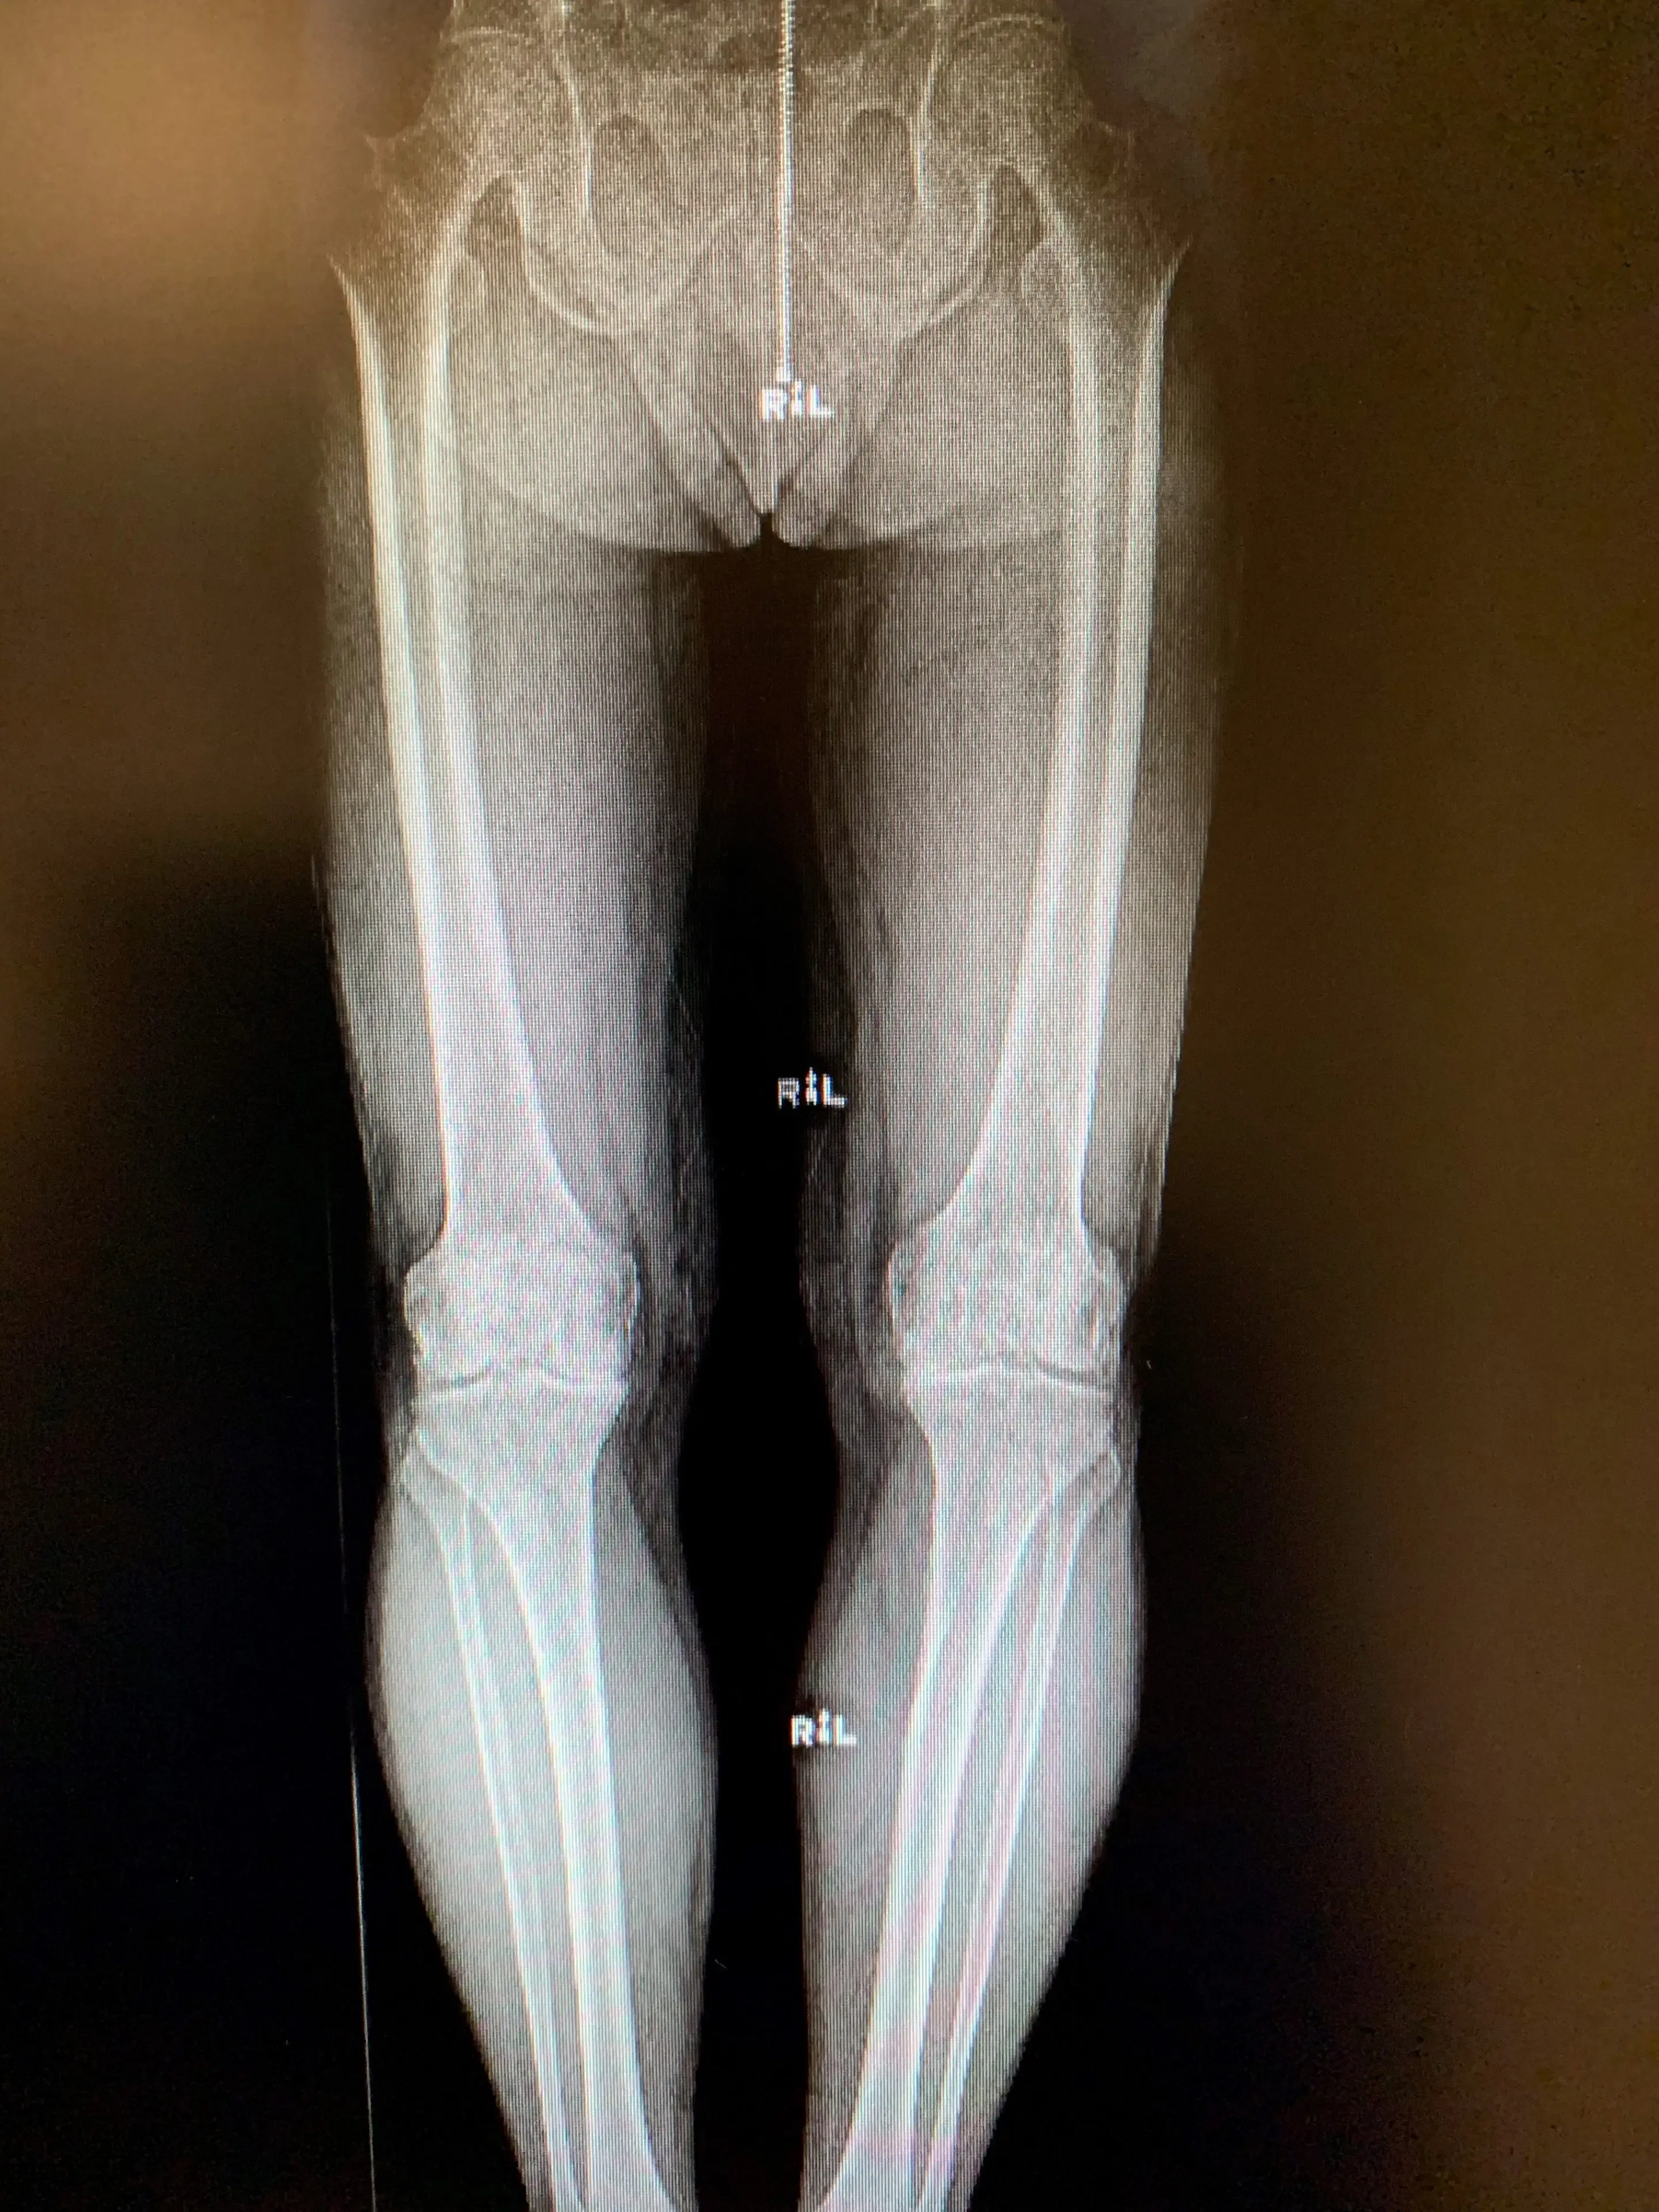

Sus radiografías de película sencillas revelaron cambios artríticos en ambas rodillas confinados a su compartimento medial. La extensión de su artritis era aproximadamente igual en ambas rodillas y no presentaba deformidades radiográficas importantes.

Su examen físico fue en gran parte discreto, salvo por cierta sensibilidad en la línea articular medial en ambos lados. Específicamente, no tenía contractura de flexión y su LCA estaba funcionalmente intacto. Tenía una pequeña alineación varus totalmente corregible en ambas rodillas.

Preoperatorio

Reemplazo bilateral simultáneo de rodilla unicóndilo en un hombre de 67 años.